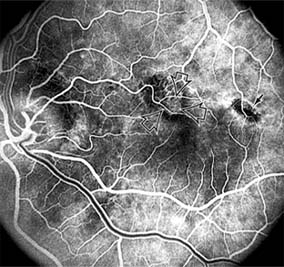

Chapter 10: Retina DISEASES OF THE MACULA AGE-RELATED MACULAR DEGENERATION Age-related macular degeneration is the leading cause of permanent blindness in the elderly. The exact cause is unknown, but the incidence increases with each decade over age 50. Other associations besides age include race (usually Caucasian), sex (slight female predominance), family history, and a history of cigarette smoking. The disease includes a broad spectrum of clinical and pathologic findings that can be classified into two groups: nonexudative ("dry") and exudative ("wet"). Although both types are progressive and usually bilateral, they differ in their manifestations, prognosis, and management. The more severe exudative form accounts for approximately 90% of all cases of legal blindness due to age-related macular degeneration. 1. NONEXUDATIVE MACULAR DEGENERATION Nonexudative age-related macular degeneration is characterized by variable degrees of atrophy and degeneration of the outer retina, retinal pigment epithelium, Bruch's membrane and choriocapillaris. Of the ophthalmoscopically visible changes in the retinal pigment epithelium and Bruch's membrane, drusen are the most typical (Figure 10-1). Drusen are discrete, round, yellow-white deposits of variable size beneath the pigment epithelium and are scattered throughout the macula and posterior pole. With time, they may enlarge, coalesce, calcify, and increase in number. Histopathologically, most drusen consist of focal collections of eosinophilic material lying between the pigment epithelium and Bruch's membrane; they therefore represent focal detachment of the pigment epithelium. In addition to drusen, clumps of pigment irregularly dispersed within depigmented areas of atrophy may progressively appear throughout the macula. The level of associated visual impairment is variable and may be minimal. Fluorescein angiography demonstrates irregular patterns of retinal pigment epithelial hyperplasia and atrophy. Electrophysiologic testing in most patients is normal. There is no generally accepted treatment or means of prevention of this type of macular degeneration. Laser retinal photocoagulation appears to have a beneficial effect on drusen but has not yet been shown to improve visual outcome. Although high plasma levels of antioxidants are associated with a reduced risk of age-related macular degeneration, the use of vitamin supplements does not appear to be preventive. Most patients with macular drusen never experience significant loss of central vision; the atrophic changes may stabilize or progress slowly. However, the exudative stage may develop suddenly at any time, and in addition to regular ophthalmic examinations, patients are given an Amsler grid ( 2. EXUDATIVE MACULAR DEGENERATION Although patients with age-related macular degeneration usually manifest nonexudative changes only, the majority of patients who experience severe vision loss from this disease do so from the development of subretinal neovascularization and related exudative maculopathy. Serous fluid from the underlying choroid can leak through small defects in Bruch's membrane, causing focal detachment of the pigment epithelium. Additional fluid may lead to further separation of the overlying sensory retina, and vision usually decreases if the fovea is involved. Retinal pigment epithelial detachments may spontaneously flatten, with variable visual results, and leave a geographic area of depigmentation at the involved site. Ingrowth of new vessels from the choroid into the subretinal space is the most important change that predisposes patients with drusen to macular detachment and irreversible loss of central vision. These new vessels grow in a flat cartwheel or sea-fan configuration away from their site of entry into the subretinal space. The clinical changes of early subretinal neovascularization are subtle and may be easily overlooked; during this occult stage of new vessel formation, the patient is asymptomatic, and the new vessels may not be apparent either ophthalmoscopically or angiographically. The ophthalmologist must maintain a high index of suspicion that subretinal neovascularization is present whenever a patient with evidence of age-related macular degeneration has sudden or recent central vision loss, including blurred vision, distortion, or a new scotoma. If the fundus examination reveals subretinal blood, exudate, or a grayish-green choroidal lesion in the macula, there is great likelihood that neovascularization is present, and a fluorescein or indocyanine green angiogram should be obtained promptly to determine if a treatable lesion can be identified. Although some subretinal neovascular membranes may spontaneously regress, the natural course of subretinal neovascularization in age-related macular degeneration is toward irreversible loss of central vision over a variable period of time. The sensory retina may be damaged by long-standing edema, detachment, or underlying hemorrhage. Furthermore, a hemorrhagic detachment of the retina may undergo fibrous metaplasia, resulting in an elevated subretinal mass called a disciform scar. This elevated fibrovascular mound of variable size represents the cicatricial end stage of exudative age-related macular degeneration. It is usually centrally located and results in permanent loss of central vision. Treatment In the absence of subretinal neovascularization, no medical or surgical treatment of serous retinal pigment epithelial detachment is of proved benefit. The use of parenteral alpha interferon, for example, has not been effective for this disease. However, if a well-defined extrafoveal ( Krypton laser photocoagulation of juxtafoveal (<200 Following successful photocoagulation of a subretinal neovascular membrane, recurrent neovascularization either contiguous with or remote from the laser scar may occur in one-half of cases by 2 years. Recurrence is often accompanied by severe vision loss, so that careful monitoring with Amsler grids, ophthalmoscopy, and angiography is essential. Low-dose radiotherapy has provided encouraging results in patients with subfoveal neovascularization. Patients with impaired central vision in both eyes may benefit from a variety of low vision aids. CENTRAL SEROUS CHORIORETINOPATHY Central serous chorioretinopathy is characterized by serous detachment of the sensory retina as a consequence of focal leakage of fluid from the choriocapillaris through a defect in the retinal pigment epithelium (Figures 10-2 and 10-3). This disease typically affects young to middle-aged men and may be related to life stress events. Most patients present with the sudden onset of blurred vision, micropsia, metamorphopsia, and central scotoma. Visual acuity is often only moderately decreased and may be improved to near-normal with a small hyperopic correction. The diagnosis is made by slitlamp examination of the fundus; the presence of serous detachment of the sensory retina in the absence of ocular inflammation, subretinal neovascularization, an optic pit, or a choroidal tumor is diagnostic. The retinal pigment epithelial lesion appears as a small, round or oval, yellowish-gray spot that is variable in size and may be difficult to detect without the aid of fluorescein angiography. Fluorescein dye leaking from the choriocapillaris may accumulate below the pigment epithelium or sensory retina, resulting in a variety of patterns including the well-recognized smokestack configuration. Approximately 80% of eyes with central serous chorioretinopathy undergo spontaneous resorption of subretinal fluid and recovery of normal visual acuity within 6 months after the onset of symptoms. Despite normal acuity, however, many patients have a mild permanent visual defect, such as a decrease in color sensitivity, micropsia, or relative scotoma. Twenty to 30 percent of patients will have one or more recurrences of the disease, and complications-including subretinal neovascularization and chronic cystoid macular edema-have been described in patients with frequent and prolonged serous detachments. The cause of central serous chorioretinopathy is unknown; there is no convincing evidence that the disease is either infectious or due to retinal pigment epithelial dystrophy. Argon laser photocoagulation directed to the active leak significantly shortens the duration of the sensory detachment and hastens the recovery of central vision, but there is no evidence that prompt photocoagulation reduces the chance of permanent loss of visual function. Although the complications of retinal laser photocoagulation are few, it is probably not advisable to recommend immediate photocoagulation treatment in all patients with central serous chorioretinopathy. The duration and location of disease, the condition of the fellow eye, and occupational visual requirements are all considerations upon which treatment decisions are based. MACULAR EDEMA Retinal edema involving the macula may be associated with a variety of intraocular inflammatory diseases, retinal vascular diseases, intraocular surgery, inherited or acquired retinal degenerations, medications, macular membranes, or unknown causes. Macular edema may be diffuse, with nonlocalized intraretinal fluid causing thickening of the macula. When edema fluid accumulates in honeycomb-like spaces of the outer plexiform and inner nuclear layers, it is called cystoid macular edema. On fluorescein angiography, fluorescein dye leaks from the perifoveal retinal capillaries and accumulates in a flower-petal pattern about the fovea (Figure 10-4). The most widely recognized association with cystoid macular edema is intraocular surgery. Approximately 50% of eyes undergoing uneventful intracapsular cataract extraction and 20% of eyes undergoing extracapsular cataract extraction develop angiographic cystoid macular edema. Clinically significant edema usually occurs within 4-12 weeks postoperatively, but in some instances its onset may be delayed for months or years. Many patients with cystoid macular edema of less than 6 months' duration have self-limited leakage that will resolve without treatment. Topical or local (or both) anti-inflammatory therapy may be of value in restoring visual acuity in some patients with chronic postoperative macular edema. YAG laser vitreolysis (see Chapter 24) and surgical vitrectomy may be of benefit when the macular edema is associated with vitreous tissue incarcerated in the cataract wound or adherent to anterior segment structures. When an intraocular lens implant is the cause of postoperative macular edema due to its design, positioning, or inadequate fixation, removal of the lens implant can be considered. INFLAMMATORY DISORDERS INVOLVING THE MACULA Presumed Ocular Histoplasmosis Syndrome (Figures 10-5, 10-6 and 10-7) In this disease, serous and hemorrhagic detachments of the macula are associated with multiple peripheral atrophic chorioretinal scars and peripapillary chorioretinal scarring (see Chapter 7). The syndrome usually occurs in healthy patients between the third and sixth decades of life, and the scars are probably caused by an antecedent subclinical systemic infection with Histoplasma capsulatum. The macular detachments are due to subretinal neovascularization, and the visual prognosis depends on the proximity of the neovascular membrane to the center of the fovea. If the membrane extends inside the foveal avascular zone, only 15% of eyes will retain 20/40 vision. A macular scar may change over time, and 10% of patients with normal maculae will develop new atrophic scars in this region. The relative risk of developing macular subretinal neovascularization in the second eye of an affected patient is significant, and these patients should be instructed in the frequent use of the Amsler grid and the importance of prompt examination when changes are detected. Argon laser photocoagulation of a subretinal neovascular membrane outside the foveal avascular zone in symptomatic patients is of value in preventing severe vision loss. The surgical removal of submacular membranes may prove useful in preserving vision. Acute Multifocal Posterior Placoid Pigment Epitheliopathy (AMPPPE) AMPPPE typically affects healthy young patients who develop rapidly progressive bilateral vision loss in association with ophthalmoscopically visible multifocal flat gray-white subretinal lesions involving the pigment epithelium (Figure 10-8). The cause of this disease, which in many instances is associated with evidence of an influenza-like illness, is unknown; the course and nature of the illness suggests the possibility of viral infection. The characteristic feature of the disease is the rapid resolution of the fundus lesions and a delayed return of visual acuity to near-normal levels. Although the prognosis for visual recovery in this acute self-limited disease is good, many patients will identify small residual paracentral scotomas when carefully tested. Extensive pigmentary changes remaining during the late stages of AMPPPE may mimic widespread retinal degeneration; the clinical history and normal electrophysiologic findings aid in this differential diagnosis. Geographic Helicoid Peripapillary Choroidopathy This is a chronic progressive and recurrent multifocal inflammatory disease of the retinal pigment epithelium, choriocapillaris, and choroid. It characteristically involves the juxtapapillary retina and extends radially to involve the macula and peripheral retina. The active stage manifests itself as sharply demarcated gray-yellow lesions with irregular borders that appear to involve the pigment epithelium and choriocapillaris. Vitritis, anterior uveitis, and subretinal neovascularization have been associated with this disorder. Involvement is usually bilateral, and the cause is unknown. The natural history of this indolent inflammatory disease is variable and may correlate with the presence of disease in the fellow eye. Local or systemic corticosteroid treatment may be of benefit when active inflammation is present; laser photocoagulation is administered as indicated for the complication of subretinal neovascularization. Vitiliginous Chorioretinitis (Birdshot Retinochoroidopathy) This is a syndrome characterized by diffuse cream-colored patches at the level of the pigment epithelium and choroid, retinal vasculitis associated with cystoid macular edema, and vitritis. The associations with HLA-A29 and with retinal S-antigen suggest that this disease has a genetic predisposition and that retinal autoimmunity plays a role in its manifestations. In many cases, electroretinography, electro-oculography, and dark adaptation studies are abnormal. The course of the disease is that of exacerbation and remission with variable visual outcomes; visual loss has been attributed to chronic cystoid macular edema, optic atrophy, macular scarring, or subretinal neovascularization. Corticosteroid therapy has not proved effective against this disease. Acute Macular Neuroretinopathy Acute macular neuroretinopathy is characterized by the acute onset of paracentral scotomas and mild visual acuity loss accompanied by wedge-shaped parafoveal retinal lesions in the deep sensory retina of one or both eyes. The macular lesions are subtle, reddish-brown, and best seen with a red-free light. The patients are usually young adults with a history of acute viral illness. While the retinal lesions may fade, the scotomas tend to persist and remain symptomatic. Multiple Evanescent White Dot Syndrome This is an acute and self-limited unilateral disease that affects mainly young women and is characterized clinically by multiple white dots at the level of the pigment epithelium, vitreal cells, and transient electroretinographic abnormalities. The cause is unknown. There is no evidence of associated systemic disease. The retinal lesions gradually regress in a matter of weeks, leaving only minor retinal pigment epithelial defects. ANGIOID STREAKS Angioid streaks appear as irregular, jagged tapering lines that radiate from the peripapillary retina into the macula and peripheral fundus (Figure 10-9). The streaks represent linear crack-like dehiscences in Bruch's membrane. The lesions are rarely noted in children and probably develop in the second or third decade of life. Early in the disease the streaks are sharply outlined and red-orange or brown. Subsequent fibrovascular tissue growth may partially or totally obscure the streak margins. Nearly 50% of patients with angioid streaks have an associated systemic disease. Pseudoxanthoma elasticum, Paget's disease of bone, Ehlers-Danlos syndrome, and several hemoglobinopathies and hemolytic disorders have been associated with this retinal disease, but the most common association is with age-related degeneration of Bruch's membrane. Patients with angioid streaks should be warned of the potential risk of choroidal rupture from even relatively mild eye trauma. Older patients with the disease are at risk of developing serous and hemorrhagic detachments of the retina as a consequence of subretinal neovascularization. Laser treatment may be used to photocoagulate extrafoveal neovascular membranes; however, other neovascular membranes are likely to occur. Prophylactic treatment of angioid streaks before subretinal neovascularization develops is not recommended. MYOPIC MACULAR DEGENERATION Pathologic myopia is one of the leading causes of blindness in the United States and is characterized by progressive elongation of the eye with subsequent thinning and atrophy of the choroid and pigment epithelium in the macula. Peripapillary chorioretinal atrophy and linear breaks in Bruch's membrane ("lacquer cracks") are characteristic findings on ophthalmoscopy (Figure 10-10). The degenerative changes of the macular pigment epithelium resemble those found in the older patient with age-related macular degeneration. A characteristic lesion of this disease is a raised, circular, pigmented macular lesion called a Fuchs spot. Most patients are in the fifth decade when the degenerative macular changes cause a slowly progressive loss of vision; rapid loss of visual acuity is usually caused by serous and hemorrhagic macular degeneration overlying a subretinal neovascular membrane. Fluorescein angiography in patients with pathologic myopia may show delayed filling of choroidal and retinal blood vessels. Angiography is helpful in identifying and locating the site of subretinal neovascularization in patients who develop serous or hemorrhagic detachments of the macula. Because of the frequent close proximity of the subretinal neovascular membrane to the foveola in these patients, laser photocoagulation may not be possible. As subretinal neovascular membranes tend to remain small and because photocoagulation-associated chorioretinal atrophy tends to progress in patients with pathologic myopia, retinal laser treatment is not as beneficial as in other diseases associated with macular subretinal neovascularization. The chorioretinal changes of pathologic myopia predispose the retina to breaks and thus to retinal detachment. Peripheral retinal findings may include paving stone degeneration, pigmentary degeneration, and lattice degeneration. Retinal breaks usually occur in areas involved with chorioretinal lesions, but they also arise in areas of apparently normal retina. Some of these breaks, particularly those of the "horseshoe" and round retinal tear type, will progress to rhegmatogenous retinal detachment. MACULAR HOLE A macular hole is a partial or full-thickness absence of the sensory retina in the macula. This disorder occurs most often in elderly women and is associated with elevated plasma fibrinogen levels. The typical finding on biomicroscopy of the symptomatic eye is a full-thickness, round or oval, sharply defined hole measuring one-third disk diameter in the center of the macula, which may be surrounded by a ring detachment of the sensory retina (Figure 10-11). With a full-thickness macular hole, visual acuity is impaired and metamorphopsia, as well as a central scotoma, are present on the Amsler grid. An operculum of retinal tissue may overlie the macular hole. Tangential traction from epiretinal vitreous cortex plays an important role in the pathogenesis of macular hole. Early stages of macular hole formation, such as a deep foveal yellow spot or ring, may be reversible as the posterior vitreous cortex spontaneously separates from the retina. Therapy for macular hole disease involves reattaching and potentially restoring function to the retina overlying the cuff of subretinal fluid surrounding the hole. While the anatomic results of vitrectomy surgery to close macular holes are encouraging, the clinical benefits are still under study. EPIRETINAL MACULAR MEMBRANES Fibrocellular membranes may proliferate on the surface of the retina, either in the macula or peripheral retina. Contraction or shrinkage of these epiretinal membranes may cause varying degrees of visual distortion, intraretinal edema, and degeneration of the underlying retina. Biomicroscopy usually shows retinal wrinkles and vessel tortuosity and may rarely also show retinal hemorrhages, cotton-wool spots, serous retinal detachment, and macular hole; a posterior vitreous detachment is nearly always present (Figure 10-12). Disorders associated with epiretinal membranes include retinal tears with or without rhegmatogenous retinal detachment, vitreous inflammatory diseases, trauma, and a variety of retinal vascular diseases. Patients with macular distortion and vision loss caused by epiretinal membrane contraction are usually left with stable visual acuity, suggesting that membrane contraction is a short-lived and self-limited process. Surgical peeling of severe epiretinal membranes can be performed successfully, but regrowth of epiretinal tissues occurs in some cases. There is no role for photocoagulation in the treatment of epiretinal macular membrane disease. TRAUMATIC MACULOPATHY Blunt trauma to the anterior segment of the eye may cause a contrecoup injury to the retina called commotio retinae. The retina develops a gray-white color that affects primarily the outer retina and may be confined to the macular area (Berlin's edema) or may involve extensive areas of the peripheral retina. The retinal whitening in the macular area may clear completely, or impairment of central vision may be permanent and associated with a pigmented retinal scar (Figure 10-13) or a macular hole. Trauma similar to that which causes Berlin's edema may also cause choroidal rupture with subretinal hemorrhage and permanent central vision loss. In addition to blunt trauma, several other traumatic injuries involving the macula are of importance. Purtscher's retinopathy is characterized by multiple patches of superficial retinal whitening and retinal hemorrhages in each eye of a patient after severe compression injury to the head or trunk. Terson's syndrome is seen in approximately 20% of patients after traumatic (or spontaneous) subarachnoid or subdural hemorrhage and is characterized by vitreous and superficial macular hemorrhage. Solar retinopathy refers to a specific foveolar lesion that occurs after sun-gazing and is best described as a usually bilateral sharply circumscribed and often irregularly shaped partial-thickness hole or depression in the center of the fovea. MACULAR DYSTROPHIES Macular dystrophies differ from degenerations in that the former are inherited, though not necessarily evident at birth, and are not associated with systemic diseases. Most often the disorder is restricted to the macula; it may be symmetric or asymmetric, but eventually both eyes are affected. In the early stages of some of these disorders the visual acuity may be reduced while the macular changes are subtle or absent on ophthalmoscopy, and the patient's complaint may be dismissed as spurious. Conversely, in other macular dystrophies, the ophthalmoscopic changes may be very striking at a time when the patient is free of visual symptoms. One method of classifying the more common macular dystrophies is to consider the presumptive anatomic layer or layers of the retina involved (Table 10-1). X-Linked Juvenile Retinoschisis This is a congenital disease of males characterized by a macular lesion called "foveal schisis." On slitlamp examination, foveal schisis appears as small superficial retinal cysts arranged in a stellate pattern accompanied by radial striae centered in the foveal area (Figure 10-14). Visual acuity is usually between 20/40 and 20/200; peripheral visual field abnormalities are present in the 50% of patients with associated peripheral retinoschisis. The posterior pole appears normal on fluorescein angiography, and this may be helpful in the clinical differentiation from cystoid macular edema. B wave abnormalities on the electroretinogram are consistent with the histopathologic finding of intraretinal splitting in the nerve fiber layer. Cone-Rod Dystrophies The cone-rod dystrophies constitute a relatively rare group of disorders that may be regarded as a single entity showing variable expressivity. Most cases are sporadic, but familial cases are usually transmitted by an autosomal dominant inheritance pattern. Cone-rod dystrophy is characterized by predominant involvement of the cone photoreceptors with progressive color vision defects and associated loss of visual acuity. A bilateral and symmetric bulls-eye pattern of depigmentation and a corresponding zone of hyperfluorescence surrounding a central nonfluorescent spot (similar to that seen in chloroquine retinopathy) are the most commonly described biomicroscopic and angiographic changes in these patients (Figure 10-15). As the disease progresses, the electroretinogram shows marked loss of cone function associated with a slight to moderate loss of rod function. Histopathologic study shows absence of macular and paramacular photoreceptors, and there is associated pigment epithelium degeneration. Fundus Albipunctatus Fundus albipunctatus is an autosomal recessive nonprogressive dystrophy characterized by a myriad of discrete small white dots at the level of the pigment epithelium sprinkled about the posterior pole and midperiphery of the retina. Patients are night-blind with normal visual acuity, normal visual fields, and normal color vision. While the electroretinogram and electro-oculogram are usually normal, dark adaptation thresholds are markedly elevated. Retinitis punctata albescens is the less common progressive variant of this dystrophy. Fundus Flavimaculatus (Stargardt's Disease) This is a bilateral and symmetric autosomal recessive disorder characterized by multiple yellow-white fleck lesions of variable size and shape confined to the retinal pigment epithelium (Figure 10-16). Many patients suffer central visual loss in childhood; however, macular involvement and the ultimate visual outcome are variable. Fluorescein angiography is important in differentiating flecks from drusen; the former are usually hypofluorescent. The electroretinogram and electro-oculogram are usually normal. Histopathologic abnormalities are confined to the pigment epithelium; the yellow flecks seen clinically are dense accumulations of lipofuscin within engorged pigment epithelial cells. Vitelliform Dystrophy (Best's Disease) Vitelliform dystrophy is an autosomal dominant disorder with variable penetrance and expressivity with onset usually in childhood. The ophthalmoscopic appearance is variable and ranges from a mild pigmentary disturbance within the fovea to the typical vitelliform or "egg yoke" lesion located within the central macula (Figure 10-17). This characteristic cyst-like lesion is generally quite round and well demarcated and contains homogeneous opaque yellow material lying at the apparent level of the retinal pigment epithelium. The "egg yoke" may degenerate and be associated with subretinal neovascularization, subretinal hemorrhage, and extensive macular scarring. Visual acuity often remains good, and the electroretinogram is normal; the distinctly abnormal electro-oculogram is the hallmark of this disease. PREVIOUS | NEXT Page: 1 | 2 | 3 | 4 | 5 | 6 | 7 | 8 | 9 10.1036/1535-8860.ch10 |